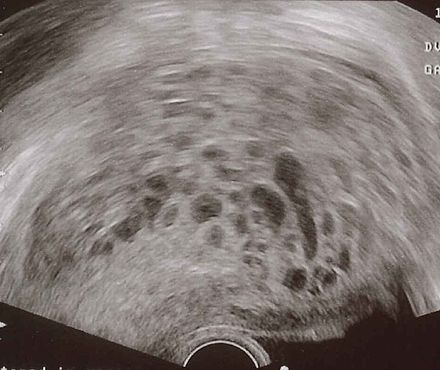

Моларна (гроздовидна) бременност

Публикувано на: 09.01.2007 Моларната бременност е патология на плацентата, причинена от проблем на оплождането на яйцеклетката ...